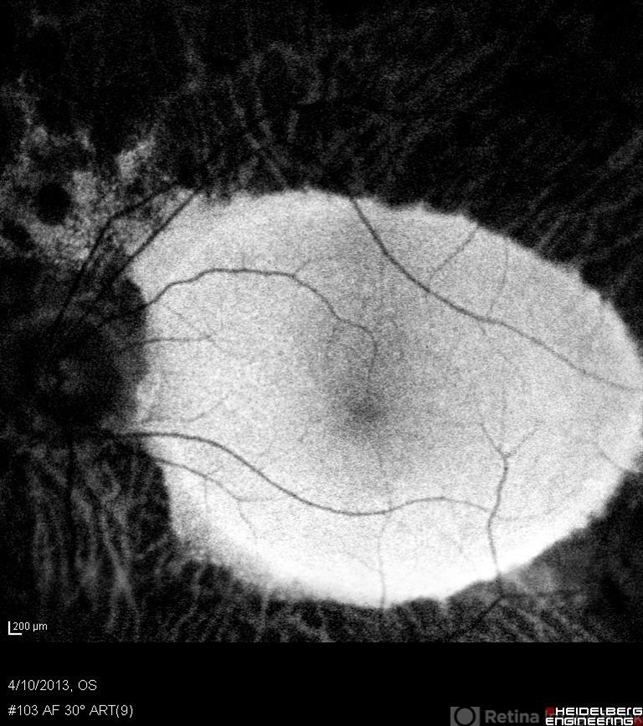

- retinitis pigmentosa, macula

- Tom Steele, CRA Midwesteye Institute, Indianapolis Indiana

- 78-year-old male with advanced retinitis pigmentosa.